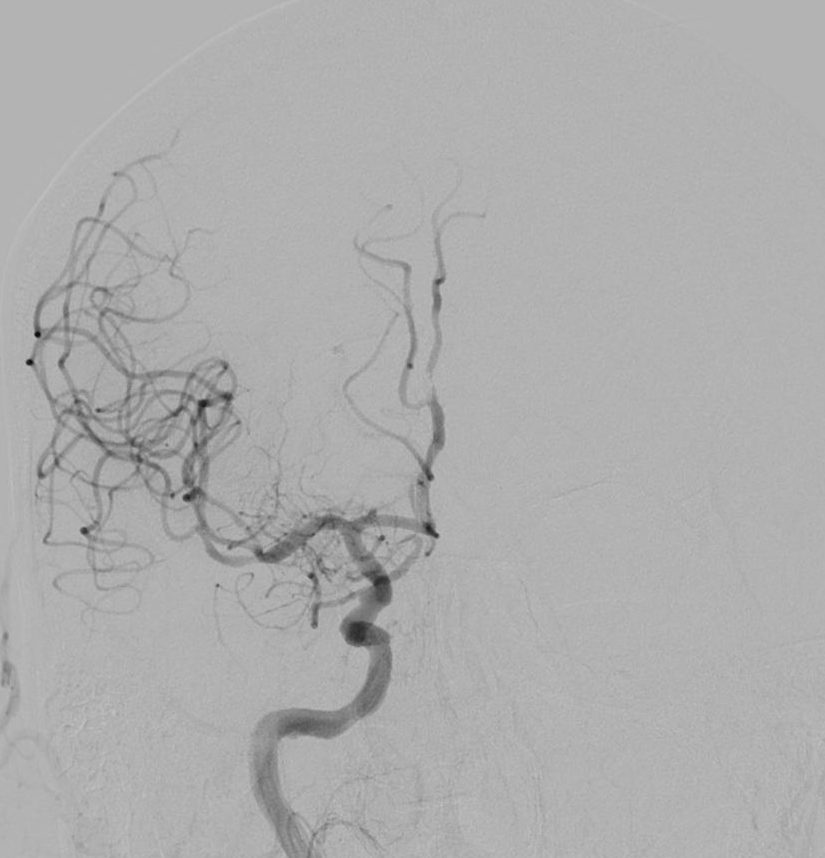

Lors de cette intervention réalisée par des radiologues spécialisés, un cathéter est inséré dans le réseau artériel, généralement par une piqure dans l’aine, et guidé jusqu’aux artères du cerveau, où il permet de retirer mécaniquement le caillot qui bloque la circulation sanguine à l’aide d’un stent et/ou d’un cathéter d’aspiration. Cette procédure vise à restaurer le flux sanguin vers la zone du cerveau affectée, minimisant ainsi les dommages cérébraux et améliorant les chances de récupération. L’intervention est réalisée sous contrôle radiologique en temps réel.

La thrombectomie intracrânienne a démontré une efficacité significative dans le traitement des AVC ischémiques. Techniquement, la recanalisation/réouverture de l’artère initialement bouchée est obtenue dans 80 à 90% des cas.